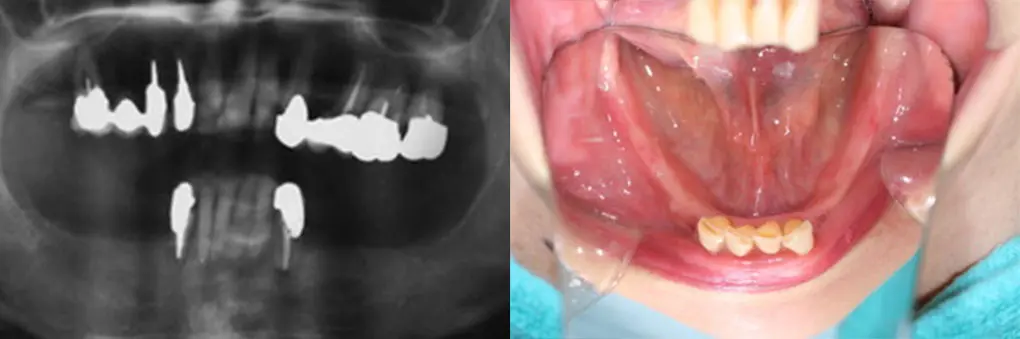

【症例3】インプラントオーバーデンチャー(50代女性)

| 主訴・背景 | 金属のバネのないしっかり咬める義歯にして欲しい |

|---|---|

| 診断・治療前の状態 | クラスプの金属が見えて審美的でない。義歯の動揺有り |

| 治療方針・計画 | 固定式のブリッジをご希望でしたが費用がかさむためインプラントオーバーデンチャーを選択。 残根歯にマグネット維持装置、インプラントを埋入してロケーター維持装置によるインプラントオーバーデンチャーの製作。 |

| 手術・処置内容 | ⚫︎ 治療部位13,21,25 インプラント3本 ⚫︎ ストローマン社 BLT TL ⚫︎ ロケーター維持装置によるオーバーデンチャー |

| 治療期間・回数 | 治療期間3カ月/治療回数5回 |

| 費用・料金(自費診療の場合) | 1,290,000円 |

| リスク・注意点・術後ケア | 義歯破損、インプラント周囲炎、定期検診 |

| 治療後の状態・経過写真 | 金属のバネも見えず、よく咬める。 術後3年経過して3カ月毎の定期検診で来院され、清掃状態も良好。 |

| まとめ・院からのコメント | きちんと3カ月に一度の定期検診に来られ、口腔清掃状態も良好 |